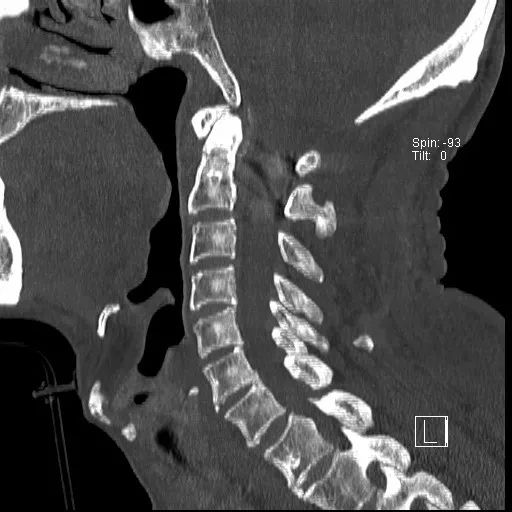

患者,男性,75岁,因外伤致颈部疼痛伴活动受限7天入院。患者入院前在当地医院确诊为:枢椎齿状突骨折Anderson-D’Alonzo分型Ⅱ型。

对于本患者来说,齿状突骨折后导致寰枢椎不稳,极易引起延髓或椎动脉损伤,严重者当场死亡。但患者同时合并严重胸腰椎后凸畸形,颈部后伸受限,不具备前路手术条件,这就给其治疗更增加了额外的困难。而由于手术部位延髓及椎动脉等血管神经密布,手术难度高、风险极大,稍有不慎,患者就会有生命危险。而患者家属在了解到手术的危险性后,曾自行到上级医院咨询专家,上级医院专家考虑围手术期死亡的风险,对于本例患者亦不愿提供手术治疗的机会。

经过全程监护和系统治疗,患者术后恢复良好,骨折解剖复位,复查X线及CT显示固定位置佳,术后3天下地行走,术后4天即出院回家休养。